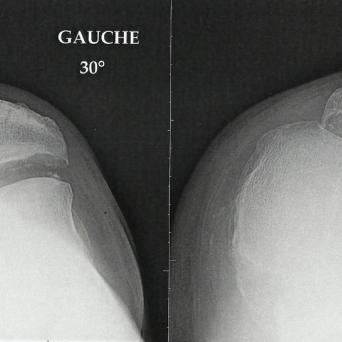

Le nombre de personnes âgées en France est en augmentation permanente avec l’allongement de la durée de vie. La prise en charge en médecine générales des seniors est complexe en raison des spécificités propres à cette population : tableaux cliniques atypiques, comorbidités multiples, polymédication,...

- Chutes chez la personne âgée : la prévention est possible !